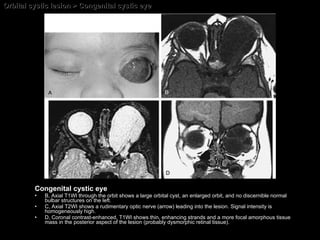

Congenital cystic eye A rare congenital anomaly. Presents at birth as a complex cyst occupying the orbit,  without any vestige of a globe .  The cyst wall is lined by cells derived from  undifferentiated retina and retinal pigment epithelium .  Some remnant  of an optic nerve–like structure and extraocular muscles may be present.

Congenital cystic eye Imaging findings; Rounded or ovoid, septated cyst The superior orbital fissure may be enlarged ipsilaterally. A rudimentary connection to a thinned optic nerve may be seen. CT Nonenhancing low-density mass MRI Hypointense on T1WI( not equal to mormal vitreous). Hyperintense on T2WI. Nonenhancing mass

Orbital cystic lesion > Congenital cystic eye Congenital cystic eye B, Axial T1WI through the orbit shows a large orbital cyst, an enlarged orbit, and no discernible normal bulbar structures on the left.  C, Axial T2WI shows a rudimentary optic nerve (arrow) leading into the lesion. Signal intensity is homogeneously high.  D, Coronal contrast-enhanced, T1WI shows thin, enhancing strands and a more focal amorphous tissue mass in the posterior aspect of the lesion (probably dysmorphic retinal tissue).